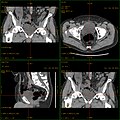

Craniale Computertomographie Abgebildet sind Felsenbein und Nasennebenhöhlen. Aufgrund der hohen Auflösung der Aufnahme des verwendeten 64-Zeilen-CTs sind selbst die Gehörknöchelchen erkennbar. -

Koronal reformatierte Darstellung von Abdomen und Becken; gut zu erkennen sind u. a. die Leber und die beiden Nieren. -

Kombination aus multiplanarer Reformatierung und sliding thin slab. Der Bildkursor befindet sich in der Harnblase. Die Originalschichtdicke beträgt 1,25 mm, dargestellt wird in allen Ansichten gemittelt (= average) in 3,7 mm bzw. 3,8 mm Dicke. -

Kombination aus multiplanarer Reformatierung und sliding thin slab. Der Bildkursor befindet sich im rechten Lungenflügel. Die sts-Bildstapel werden in Form von MIP-Darstellungen gezeigt (STS-MIP).[52] Links oben befindet sich eine VR-Darstellung der Lunge; sie zeigt einen Blick auf die koronal an Kursorposition geschnittene Lunge. -

CT-Angiographie; mittels multiplanarer Reformation (hier die sog. curved MPR) sind auch Schnittdarstellungen entlang beliebiger Gefäßverläufe möglich, wodurch die gezeigte Arteriosklerose sehr gut visualisiert werden kann.